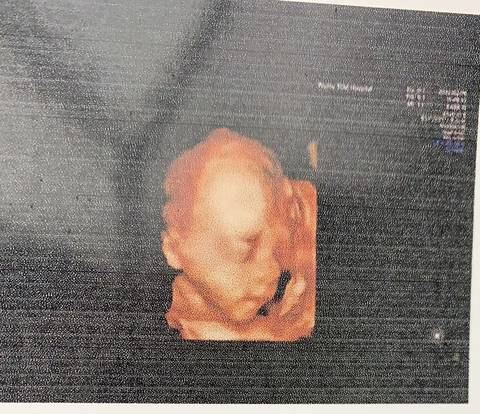

今天做了三维,三维和四维有什么区别?

journal_insert_pic_1719703338

三维跟四维彩超的话,其实一样的呢,它就是一个比较清楚一点,一般没有那么清楚。